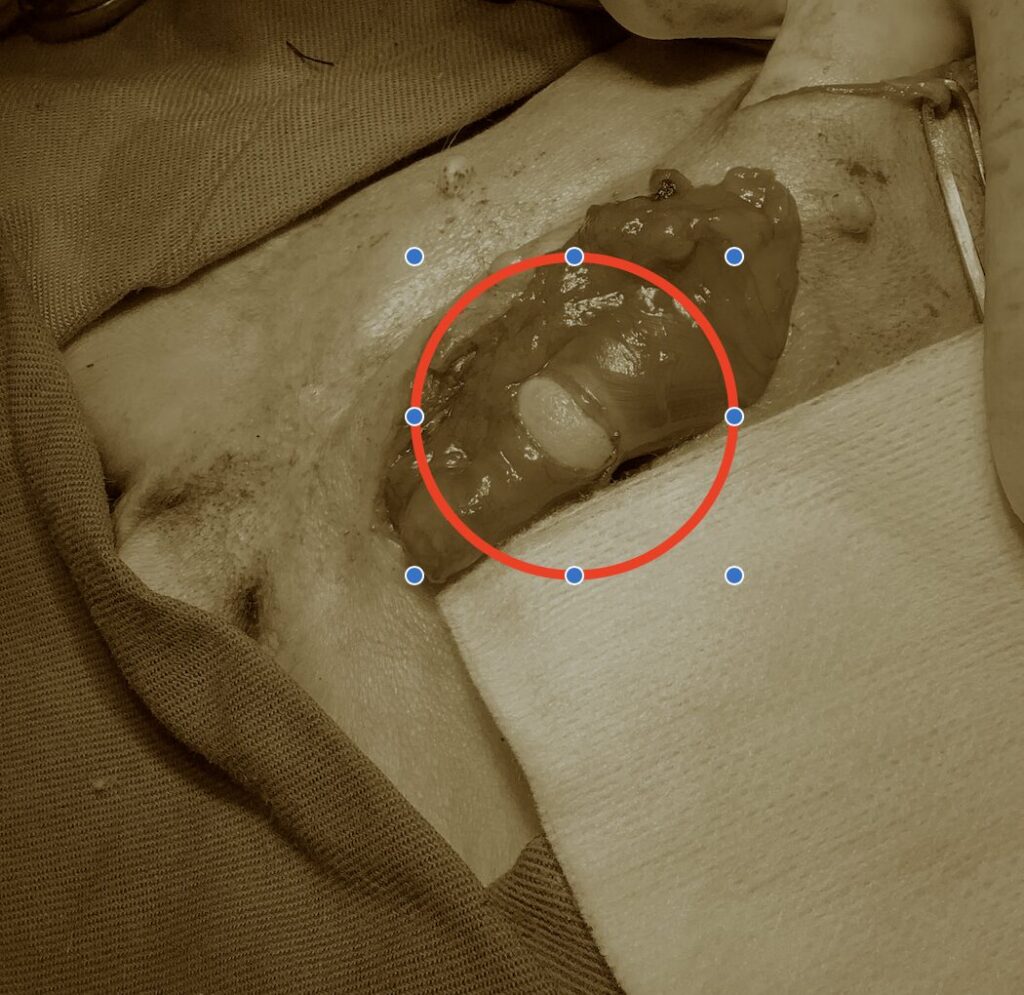

今回は鼠径ヘルニアで手術した症例を紹介します。

下腹部の乳腺が腫れているということで来院しました。

腫れている場所を超音波で確認すると腸が出ていることがわかりました。

ゆっくり押してあげると腸はお腹の中に戻って腫れは無くなりました。

鼠径ヘルニアが疑われました。

鼠径ヘルニアはヘルニア輪が小さいと飼い主さんが気づかないこともあります。

しかし今回のように大きい場合は腸や膀胱、子宮などが出てくることがあります。

それらが出てきて嵌頓すると命に関わることになります。

今回の症例は腸が出てきていたため、早めに手術した方が良いと考えられましたので

手術を行いました。

重要な動脈や静脈、神経も出てきているのでそれらを絞扼しないように気をつけて縫合をしました。

症例は術後3ヶ月ほど経過していますが、特に再発もなく元気に過ごしています。